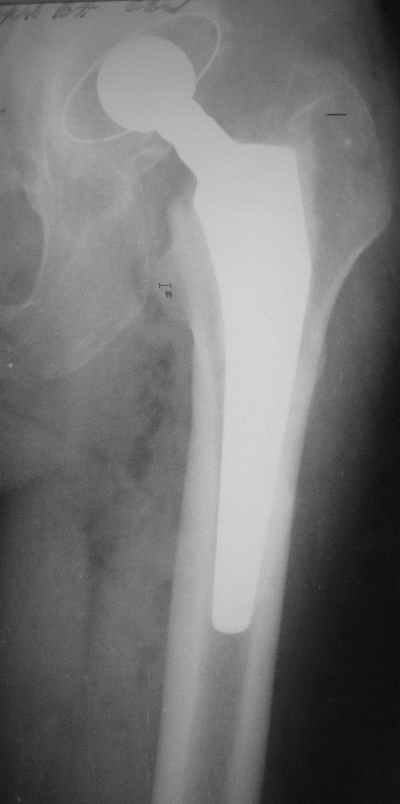

В феврале 2005 г. выполнена ревизионная артропластика, завершившаяся прогрессировавшим в течение 1-2 мес укорочением ноги. В настоящее время ходит только с костылями, при движениях в тазобедренном суставе испытывает резкие боли, ощущает хруст. Попытка осевой нагрузки бедра сопровождается ощущением "перемещения поршня" и заметным по внешним ориентирам укорочением левой ноги на 1-1,5 см.

Порекомендуйте, пожалуйста, рациональную тактику ведения больного. В каком лечебном учреждении России ему могла бы быть таки оказана полноценная помощь?